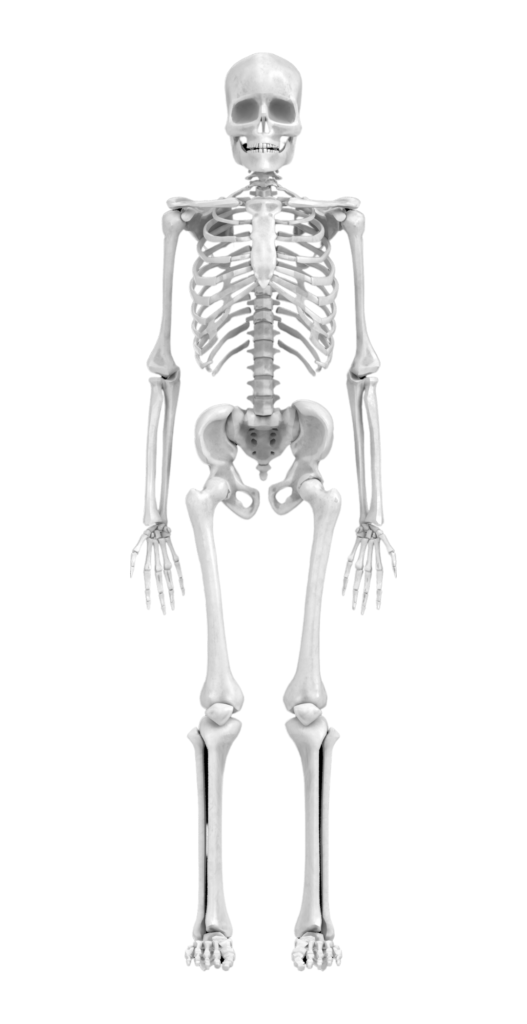

L’osteopatia è una disciplina terapeutica manuale che si focalizza sulla manipolazione di articolazioni, muscoli e tessuti del corpo per migliorare la mobilità, ridurre il dolore e stimolare la capacità di autoguarigione dell’organismo. Considera il corpo come un insieme integrato, riconoscendo l’interconnessione tra struttura e funzione.

Gli osteopati utilizzano le mani per diagnosticare, trattare e prevenire vari disturbi. Un trattamento osteopatico può includere tecniche di manipolazione articolare, mobilizzazione dei tessuti molli, tecniche miofasciali e altri approcci terapeutici mirati a ottimizzare la funzionalità globale del corpo.